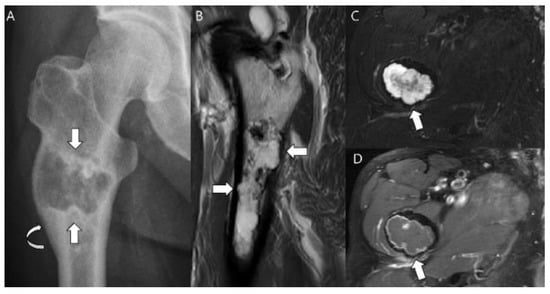

3. Diagnostic Dilemma of Chondrosarcoma Classification

3.3. Distinction between ACT/CS1 and High-Grade Chondrosarcoma